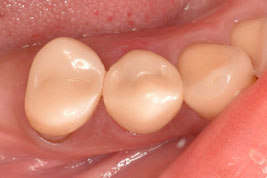

軸面の健全歯質を大幅に残したうえで、オーバーレイの形態で修復しました。インジェクションモールディング法を応用しております。直接修復なので、海外からの来院であっても、短期滞在で対応可能です。

右下4番の治療を希望されて、1年ぶりに来院してくれました。問題なく良好に経過しているとのことで、とても安心しました。

ダイレクト修復に完全移行してから、歯冠形成が大きく変わりました。アンダーカットを積極的に付与するようになり、形成のキレイさを気にせず、健全歯を最大限残す形態になりました。

インジェクションモールディング法を用いて、ダイレクトクラウンにて完了させました。ファイバーコアによる支台築造と同時にダイレクトクラウンを成形するため、歯根・築造体・クラウンとが一体化したモノブロック構造で強度を担保できます。ファイバーコアからダイレクトクラウンまで一気に進めて、だいたい2時間の施術時間です。施術中にドクターが離れることができないのですが、圧倒的な時間短縮です。